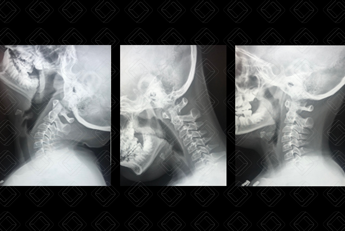

Texto alternativo para a imagem Figura 1. Créditos: Dra. Elazir Mota - Rio de Janeiro/RJ

Descrição da figura 1: As três posições na qual a radiografia de coluna cervical deve ser realizada: extensão, flexão e neutra.

Rotina radiográfica da coluna cervical: Para adequada avaliação de instabilidade da articulação atlantoaxial, o estudo deve ser efetuado com a realização de três radiografias da coluna cervical em perfil, em três diferentes posições: neutro, flexão e extensão. Nas três incidências realizadas, o radiologista mede a distância entre a face posterior do arco anterior do atlas e a face anterior do processo odontoide de C2 (o valor considerada normal é menor ou igual a 4 mm) (figuras 1 e 2).